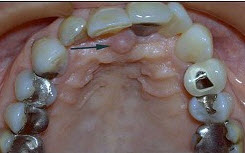

患者,女,20岁,

外伤骨折后,在口内行即刻根充术后转修复科,口腔检查,

冠2/3折断,不松动,根管内有充填物,叩(++)。余牙及咬合关系正常。